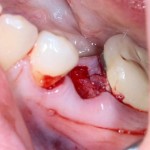

Немедленная имплантация — оптимальное решение в любой клинической ситуации